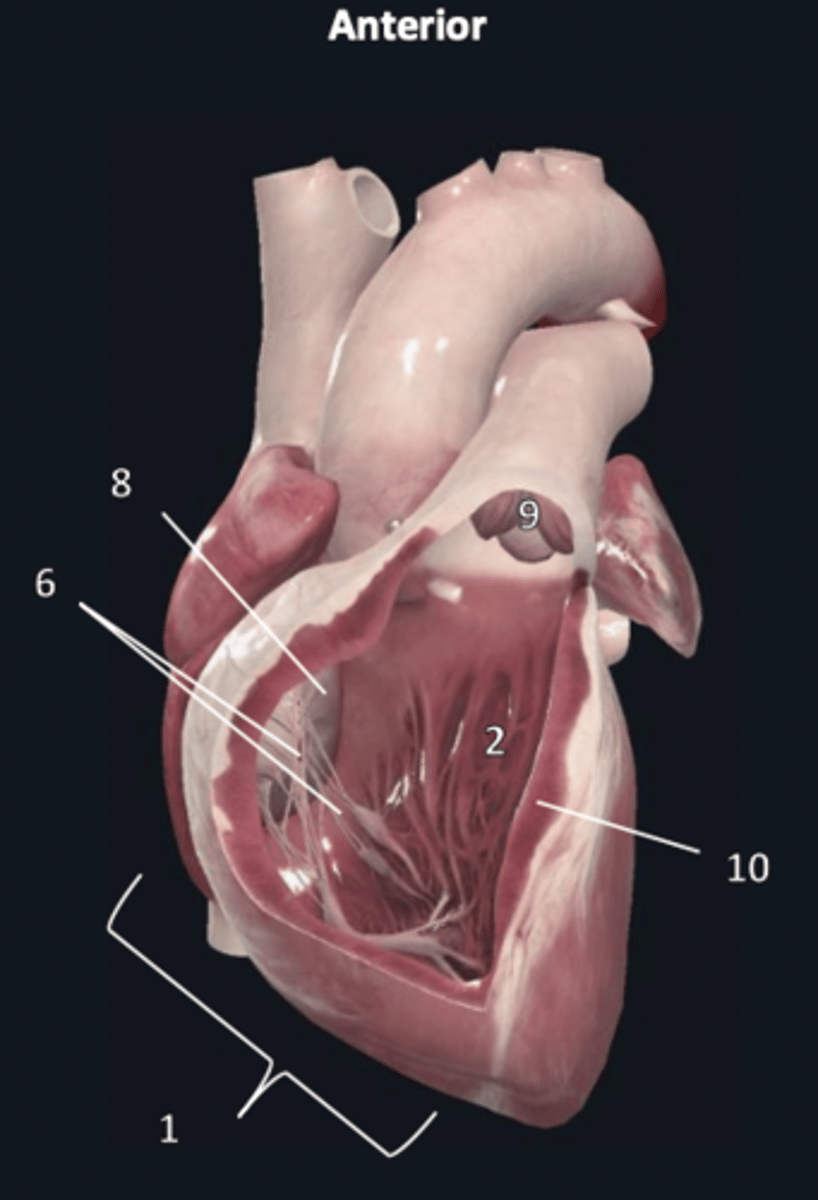

right ventricle

1

trabeculae carneae

2

septal papillary muscle

3

anterior papillary muscle

4

inferior papillary muscle

5

chordae tendineae

6

moderator band

7

tricuspid valve

8

pulmonary semilunar valve

9

interventricular septum

10